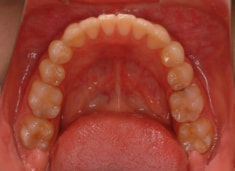

治療前